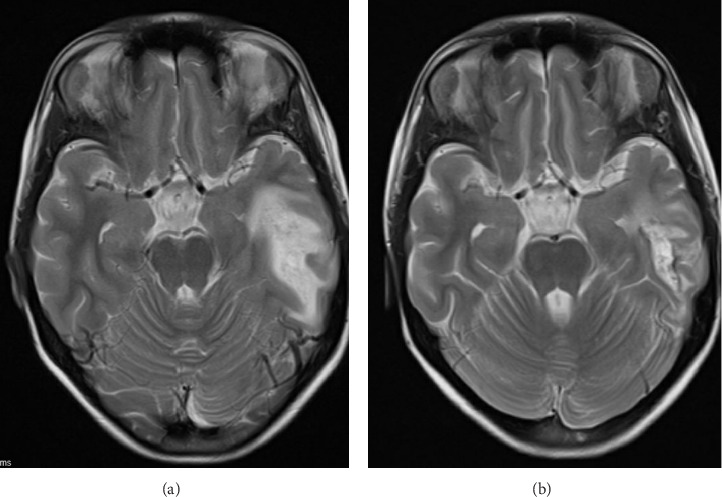

我们报告了一个10岁的女孩谁有一个非典型脱髓鞘疾病作为她的神经精神狼疮的表现。患者有4年的系统性红斑狼疮病史,10岁时出现发热和头痛,病情一度缓解。体格检查显示脑膜炎。感染性脑膜炎的广泛微生物检查未见结果。在脑磁共振成像(MRI)上发现广泛的白质高信号。在我们病例的初始阶段,由于中枢神经系统感染和狼疮的神经精神表现难以区分,在等待微生物检查结果的同时,经验性地给予静脉注射免疫球蛋白一个疗程,而不是大剂量的皮质类固醇。在开始静脉注射免疫球蛋白而不使用脉冲皮质类固醇后,发热和头痛很快消退。在活动性神经症状缓解后,她被给予6个月剂量的静脉注射免疫球蛋白(2g /kg/周期)和6个双周剂量的静脉注射环磷酰胺(500mg /m2/月)。间歇MRI显示白质高信号消退。尽管最初的表现是广泛的脱髓鞘疾病,但她成功地缓解了,没有残余的神经系统后遗症。

We reported a 10-year-old girl who had an atypical demyelinating disease as the presentation of her neuropsychiatric lupus. The patient had a 4-year history of systemic lupus erythematosus which had been on remission until she presented with fever and headache at the age of 10 years. Physical examination showed meningism. Extensive microbiological workup for infective meningitis was unrevealing. There was a radiographic finding of an extensive white matter hyperintensity on the magnetic resonance imaging (MRI) of the brain. At the initial stage of our case, as it was difficult to differentiate between infection of the central nervous system and neuropsychiatric manifestation of lupus, a course of intravenous immunoglobulin was given empirically instead of high-dose corticosteroid while awaiting the microbiological workup results. The fever and headache subsided shortly after commencement of intravenous immunoglobulin without use of pulse corticosteroid. After the active neurological symptoms remitted, she was given a total of six monthly doses of intravenous immunoglobulin at 2 g/kg/cycle and six biweekly doses of intravenous cyclophosphamide at 500 mg/m2/month. Interval MRI showed resolution of the white matter hyperintensity. Despite the extensive demyelinating disease on initial presentation, she remitted successfully without residual neurological sequelae.